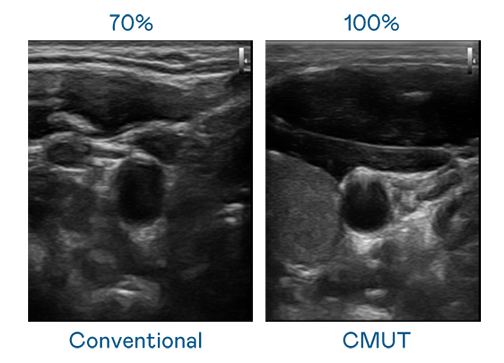

CMUT 技术是一种用电容式微机电元件来产生超音波讯号的技术。与传统 PZT 压电式技术相比,CMUT 频宽增加 30%,更宽频的超音波讯号让影像解析度大幅提升,是实现高影像品质医疗超音波扫描、促进精准医疗发展的关键技术。

大频宽带来超清晰影像

超音波影像的解析度高低,首先取决于探头能发出的讯号频宽。开云体育 CMUT 可提供高清晰的超音波讯号,提供高频宽、高灵敏度、影像纹理细节更高的超音波影像,协助医护人员缩短影像判读时间及利用精准的医疗影像进行诊断。